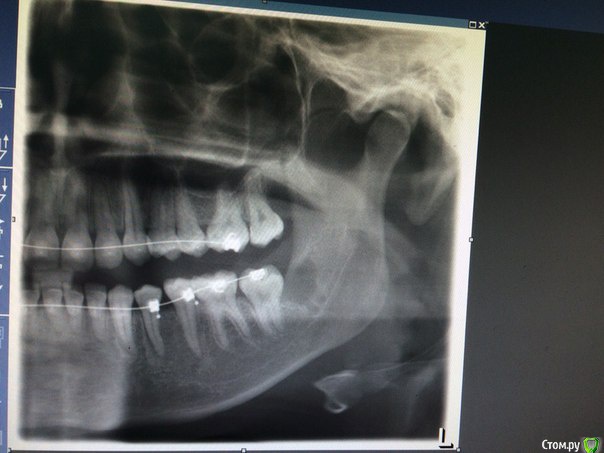

Янаyana Опубликовано 6 апреля, 2015 Поделиться Опубликовано 6 апреля, 2015 Подскажи пожалуйста мне 13 марта удалили последнюю восьмерку слева снизу.зуб был ретинированный. Удаляли полтора часа, но по удалению претензий нет.Лунка хорошо и быстро зажила, обезболивающие даже не понадобились.после удаления началась парастезия подбородка и левой части языка.подбородок прошел через 2 недели, как только сошел отек.но левая часть языка до сих пор онемевшая. Пропила пять дней мильгаму, результата не было. Врач назначил нейромультивит и хожу теперь на лазер.врач сказал, что тройничный нерв не поврежден, но воспален и пройдет все через полгода. Как только образуется костная ткань(если не ошибаюсь). Сходила к знакомому неврологу он сказал что повреждена маргинальная ветвь лицевого нерва, но в стоматологии уверяют, что эти вещи никак не связаны и что со всеми нервами все в порядке.можете ли по снимку определить поврежден ли нерв и какой или мне не о чем беспокоится?Может ли парастезия остаться навсегда или все таки пройдет?и может дадите пару советов. Ссылка на комментарий